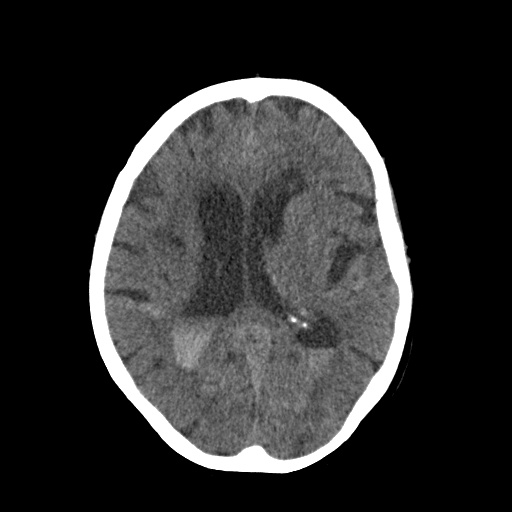

Cerebral Insight

HemoDetect: An AI based Assistant for Diagnosis of Brain Hemorrhage.